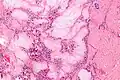

Micrograph of a gouty tophus

It appears that monosodium urate crystals trigger a distinct physiological NETosis pathway that coats them in DNA. These coated crystals then persist in tissues as a foreign body granuloma constituting gouty tophus.[4]